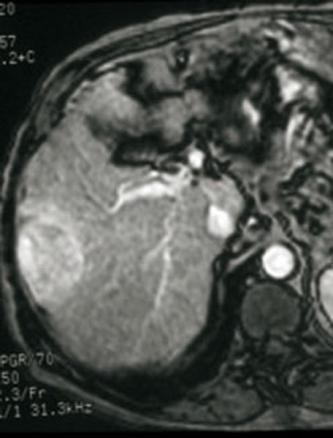

La Revue du Praticien - Eric Assenat Aspect caractéristique IRM triphasique (sans injection, temps artériel = tumeur hypervasculaire, temps portal - wash out).